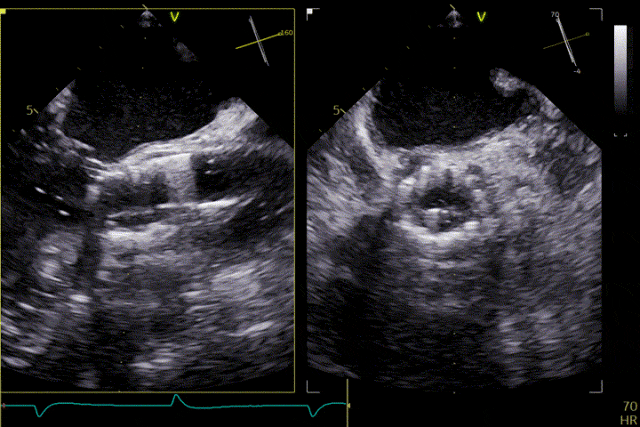

Preoperative Echocardiography

Delivery system crossing the valve

Deployment of the positioning device

Advanced into the aortic sinuses

Valve release